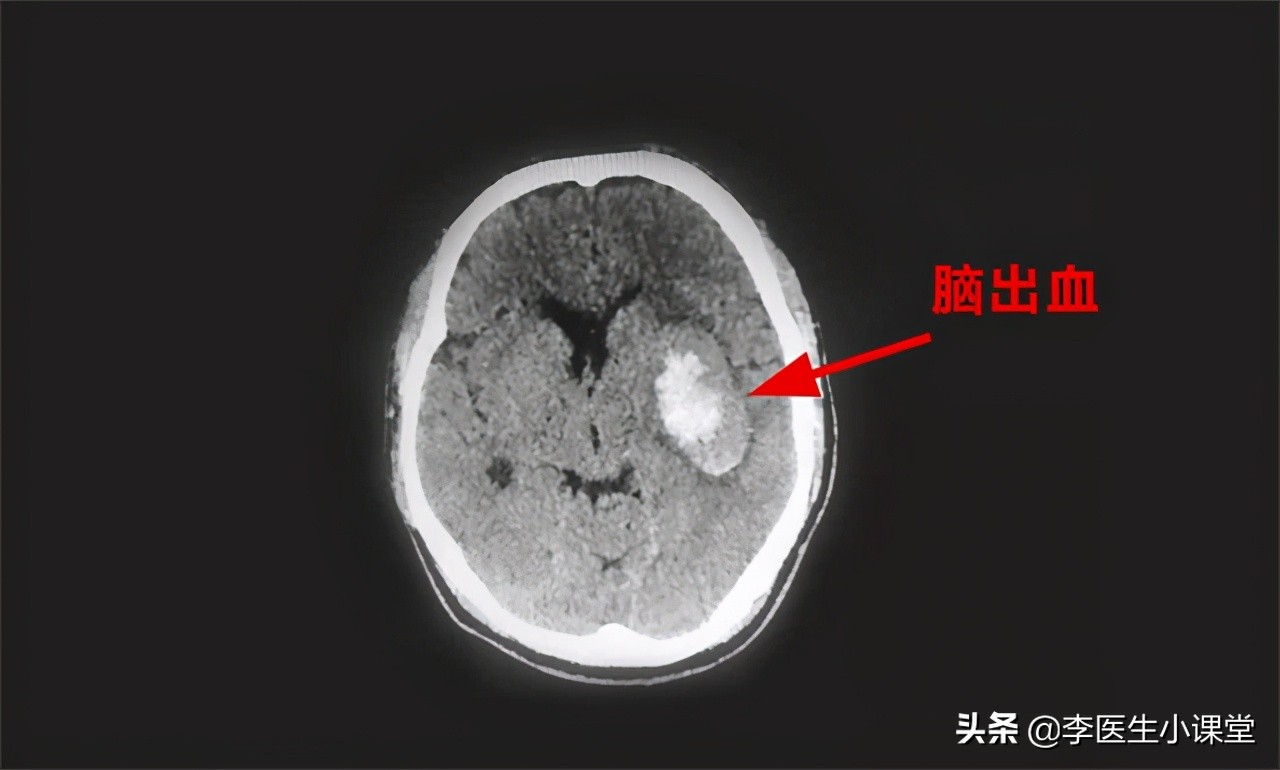

脑出血是一种 急性发作 的疾病,当脑部动脉发生破裂后会引起局部出血,出血会刺激到脑部细胞,引起 脑细胞凋亡 。脑部血管神经发生充血肿胀时,会增加周围脑组织的压力,导致 新鲜血液无法及时输送到大脑 ,从而引发脑死亡。